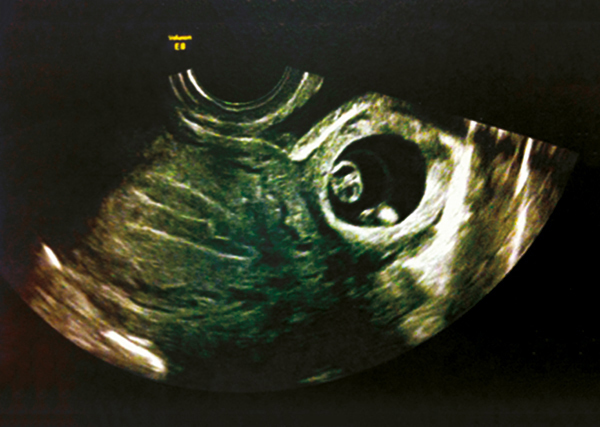

Grossesse extra-utérine : signe direct

Masse embryonnée latéro-utérine.